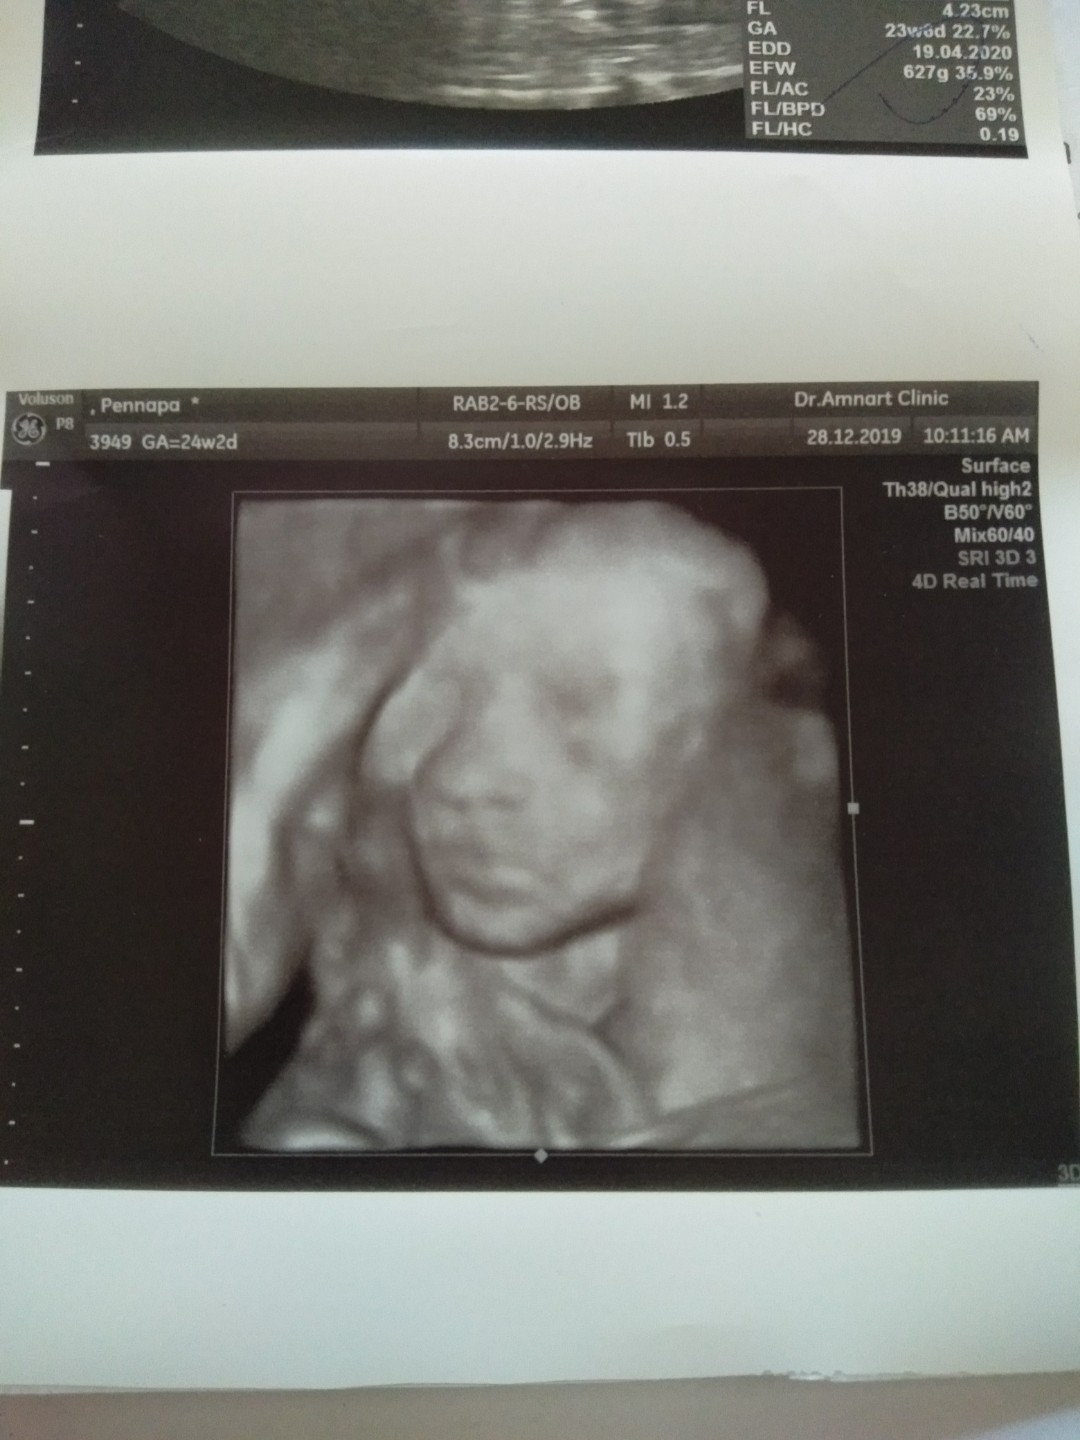

ตอน24วีคตอนนี้35วีคคะ

ลูกสาวค่ะ ซาวตอน24w